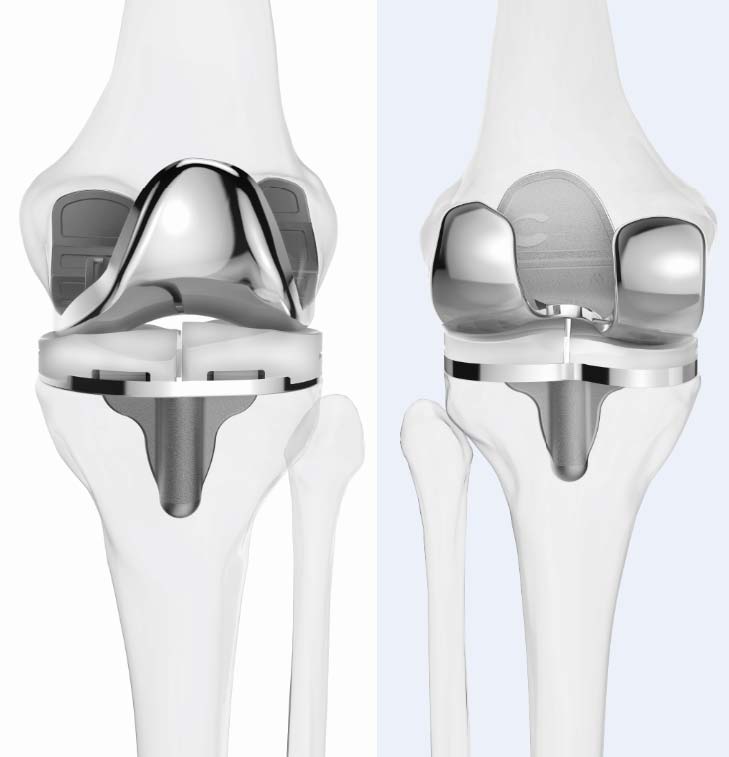

Эндопротезкунонии буғуми зону